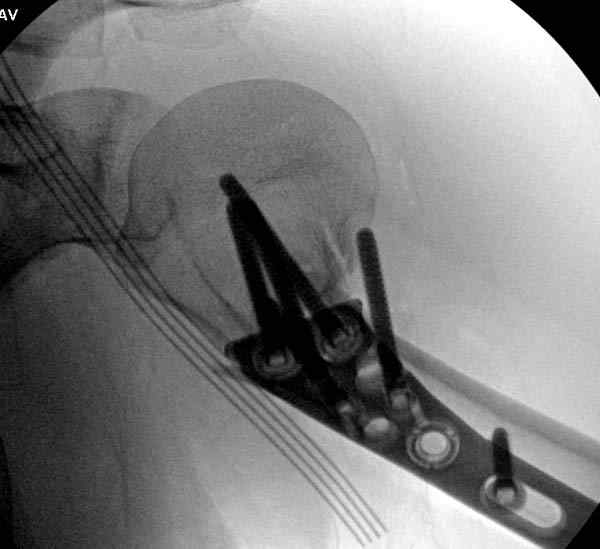

Здесь пример открытой репозиции 57 летнего с переломом плеча (1,2) смещение обнаружено на интероперационном снимке. При нормальной прямой проекция (3) угловое смещение обнаружили в аксиальной проекции (4)

После устранения смещения пластина установлена выше (5,6,7) и финальные снимки (8,9,10)